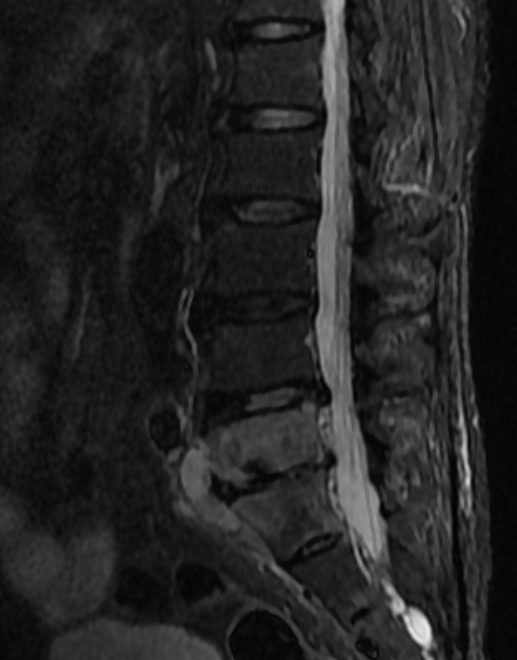

术前MRI